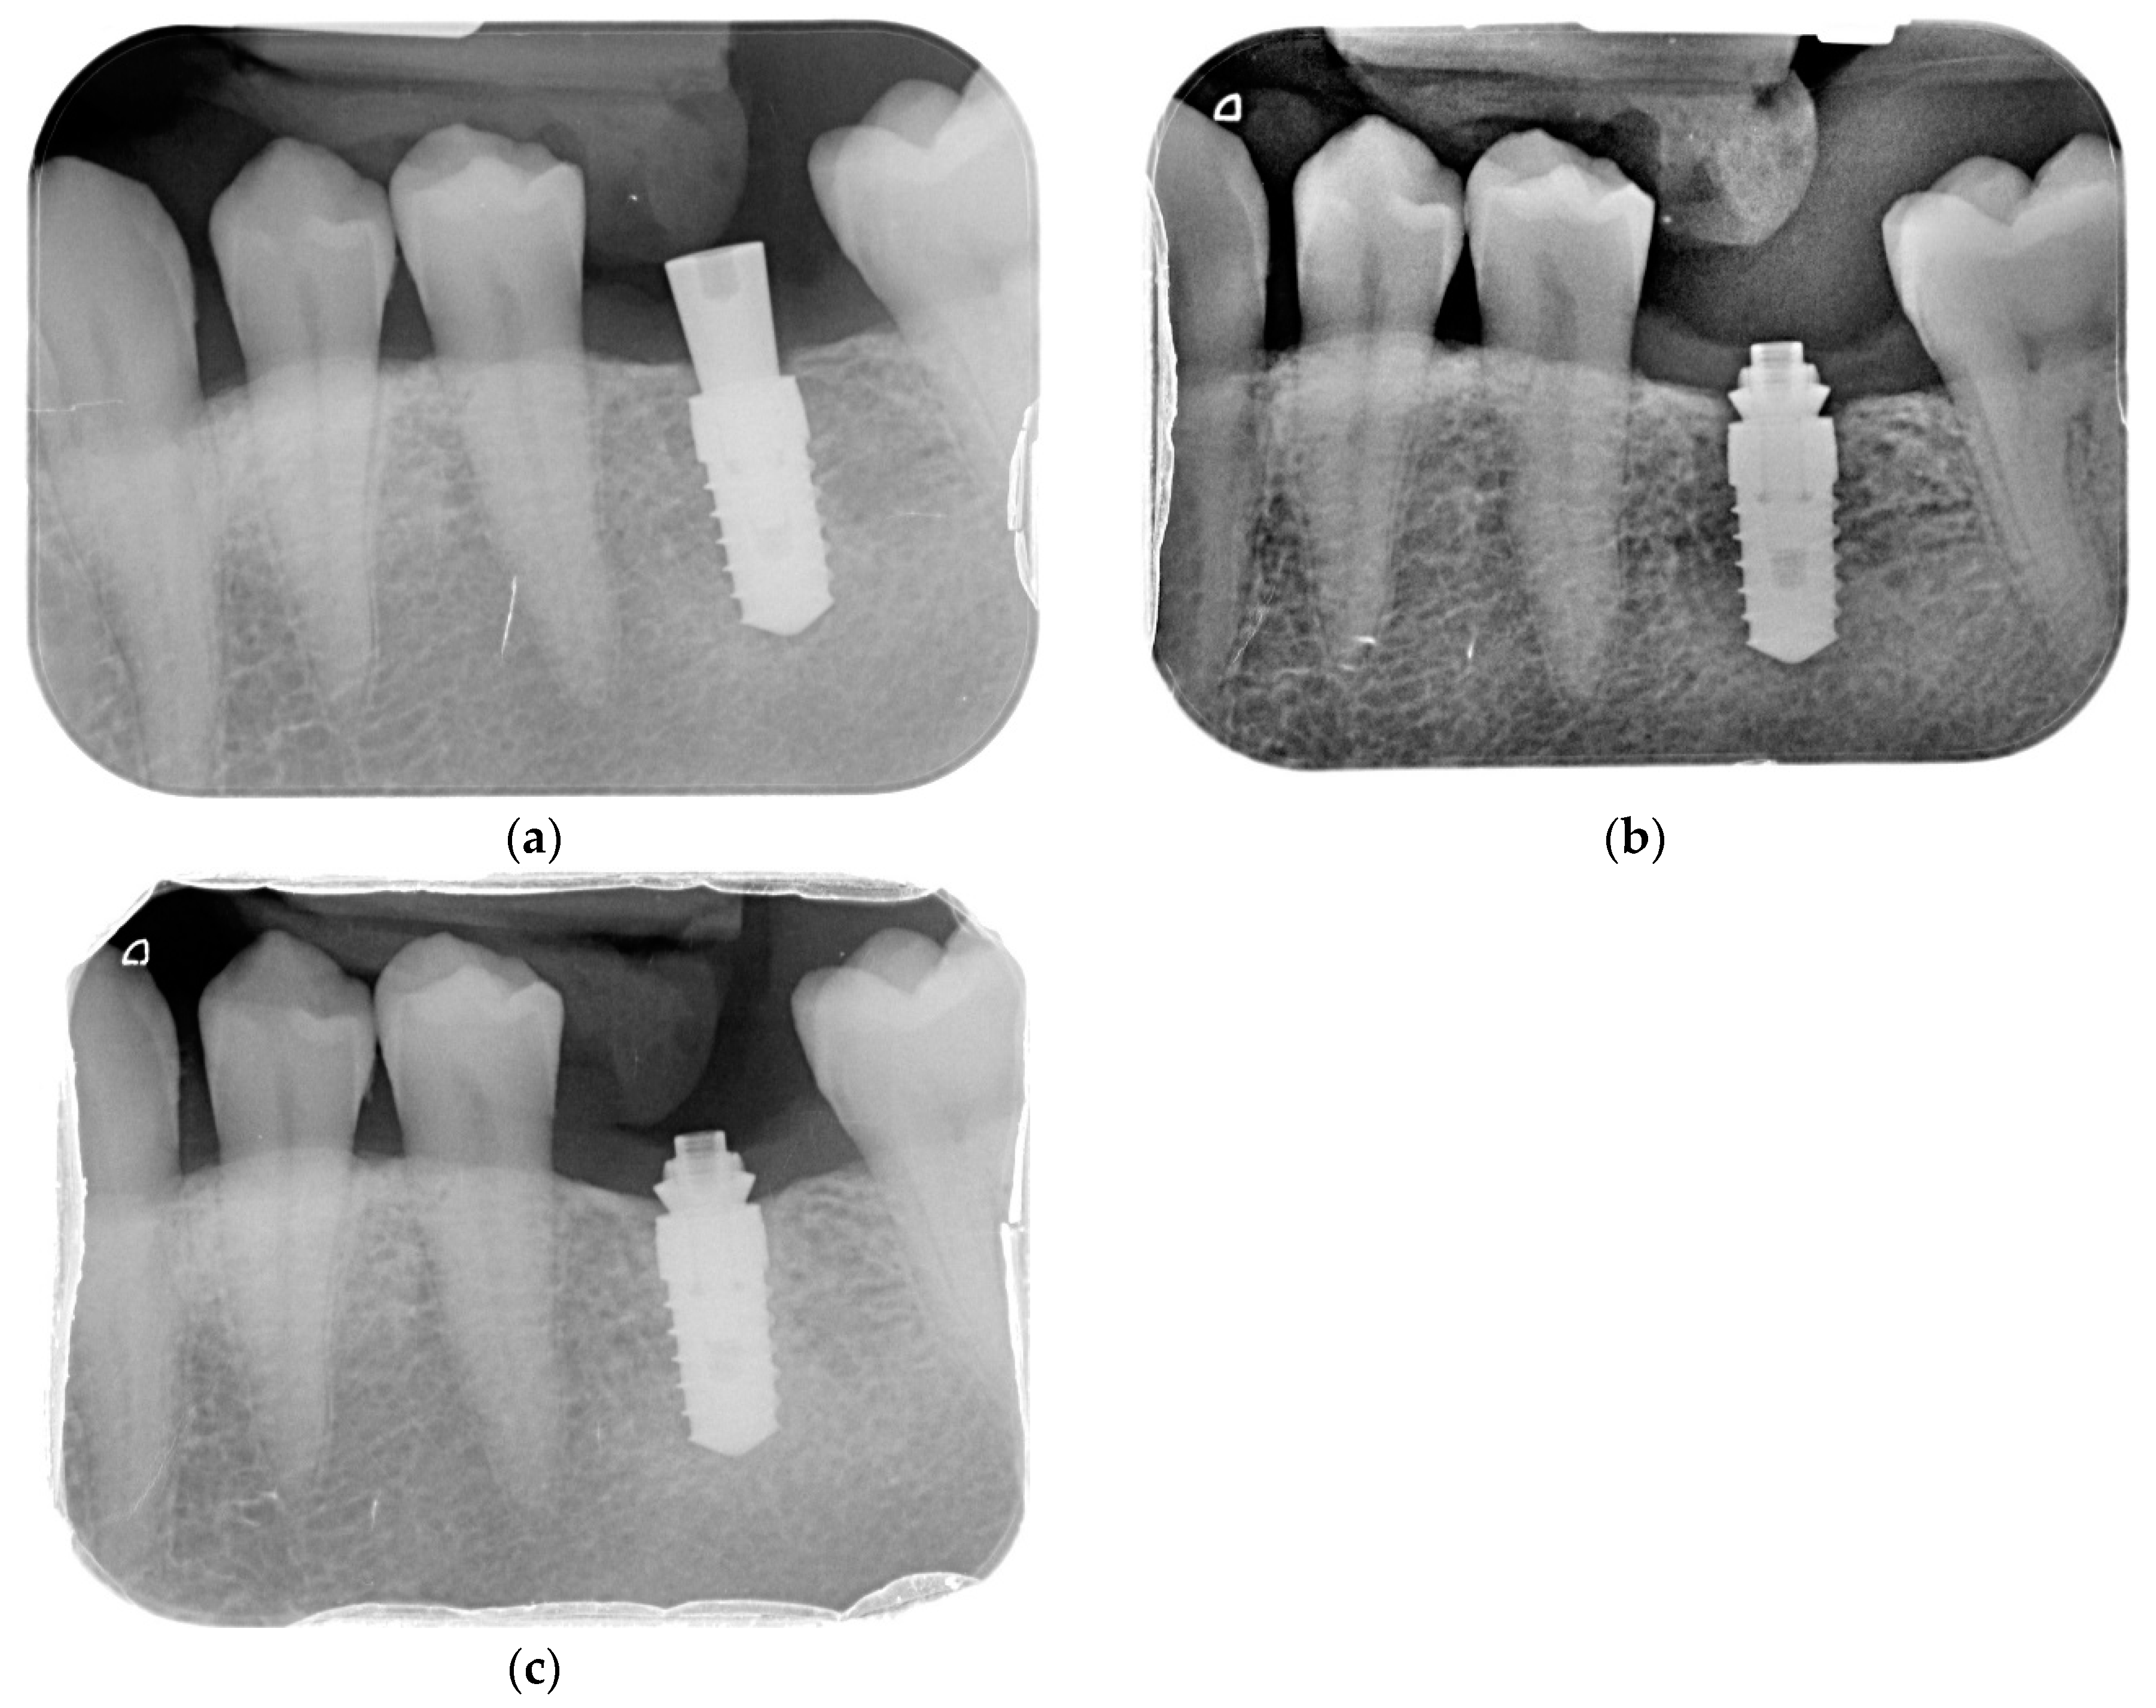

The healing abutment used (HEA group) was 5 mm high and conical in shape. The definitive abutments, placed on the day of surgery in the DEF group and on the day of the prosthesis installation in the HEA group, were Permanent® abutments (Klockner Implant System, SOADCO, Andorra), 1 or 2 mm high for single or multiple screw-retained restorations (depending on the thickness of the mucosa)—see Figure 1.

To evaluate interproximal bone levels, (individualized bite holder) standardized intra-oral radiographs were performed using the long-cone paralleling technique. The radiographs were taken before implant placement, postoperatively, at 2, 6, and 12 months—see Figure 2.

In the present study, peri-implant bone loss was investigated by studying the implants previously described, which were placed in the healed bone and screwed prosthetic at 16 weeks. The patients were randomized after implant placement and after primary stability was measured to avoid bias on the part of the operators at the time of randomization. After this, a homogeneous population was observed with no differences between the groups in regard to age, gender, bone quality, smoking, implant stability, or abutment height (Table 1). No statistically significant differences were found between the placement of the definitive abutment on the day of surgery without being removed at any other time or following the concept “One Abutment—One Time”, compared to the conventional prosthetic procedure in which the healing screw is removed at least three times. The evolution of the peri-implant bone level is similar in both groups, presenting the greatest loss in the first 6 months, with bone loss being stable in the two groups between 6 and 12 months (Figure 1). Even without statistically significant differences, the tracking in peri-implant bone loss accumulated at the one-year follow-up in the DEF group (0.36 ± 0.79 mm) is more favorable than the one in the HEA group (0.48 ± 0.71 mm).

Figure 1. (a) Permanent 1 mm unit; (b) permanent 1 mm multiple; (c) permanent 2 mm unit; (d) Permanent 2 mm multiple.